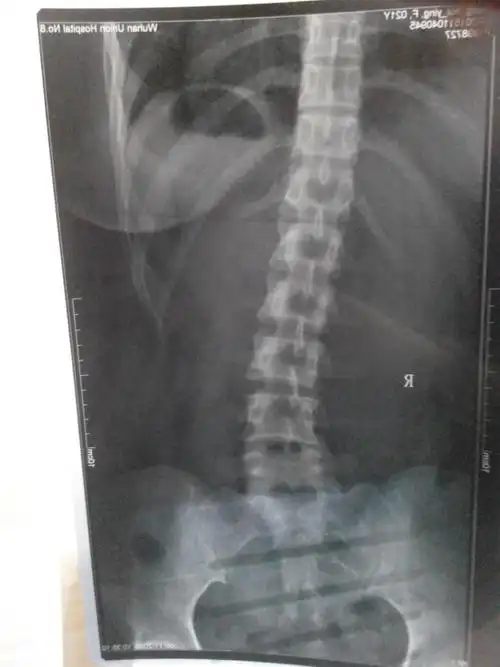

从左到右:2016年,侧弯度数35度.2017年胸弯减少到18度.

病例15岁男孩脊柱侧弯35戴gbw支具下拍片减至10

16岁高中生脊柱侧弯35度